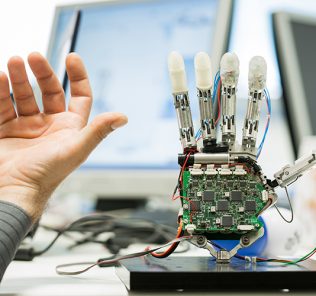

Epidural electrical stimulation involves implanting an electrode array along the lower part of the spinal cord, which ordinarily controls movement of the hips, knees, ankles and toes. Unlike similar approaches, the electrodes aren’t being used to directly stimulate the muscles. Instead, they act to reengage the spinal cord’s local nerve network, which doesn’t require input from the brain to carry out basic motor functions. The researchers surmised that this stimulation, combined with sensory input such as stepping on a treadmill could lead to movement.